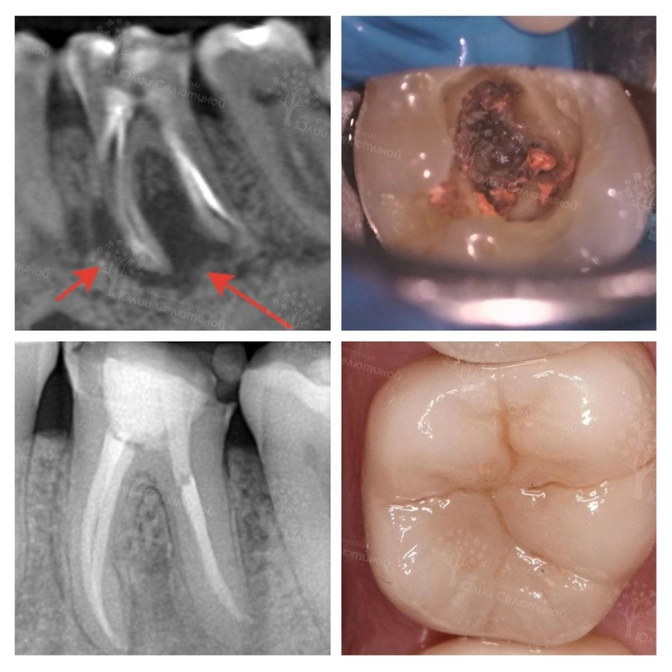

Там ему сказали, что зуб подлежит удалению, т.к. огромное воспаление периодонта ("киста").

✔️Убрала весь старый инфицированный материал;

✔️Обработала каналы;

✔️Заложила лекарство;

✔️Через две недели на повторном визите зуб запломбировала.

✔️На контрольных визитах через 4 и 8 месяцев видим положительную динамику.

????Спустя почти год полость, где была "киста", полностью заполнена новой костной тканью.